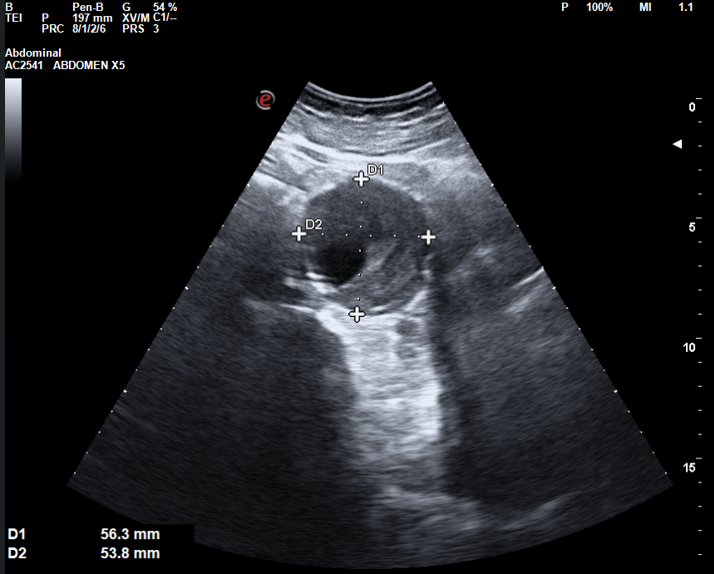

Ecografía abdominal: Hígado de tamaño y ecogenicidad normal, sin dilatación de vía biliar. Vesícula de pared fina con litiasis única en su interior. Páncreas de aspecto normal. Ambos riñones de tamaño normal, con buena diferenciación corticomedular, sin dilatación de vía urinaria ni presencia de litiasis. Bazo de tamaño y ecogenicidad normal. En el rastreo de abdomen inferior se descubre incidentalmente aorta abdominal con aumento de su diámetro (5,6 x 5,3 cm), se aprecia imagen de engrosamiento de pared compatible con trombo intramural y luz permeable de 1,7 x 1,9 cm.